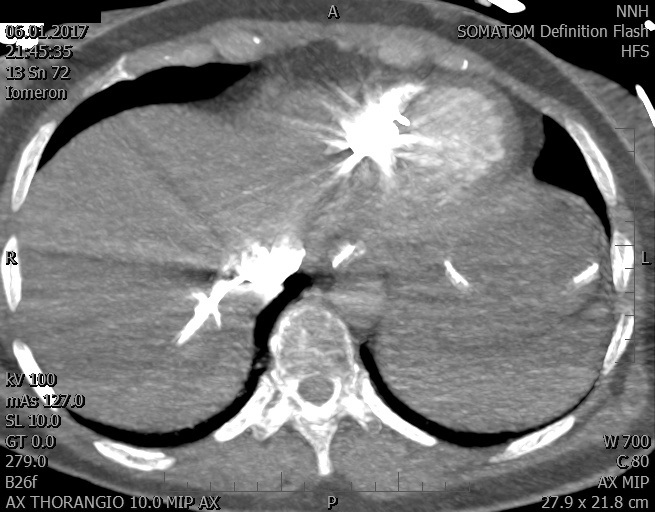

Video 1 - Akutní koronarografie prokázala normální nález na věnčitých tepnách s výjimkou suspekce na lehký spasmus na pravé koronární tepně.Echokardiograficky byla zjištěna těžká dysfunkce dilatované levé komory s nezvětšenou pravou komorou (video 2).

Video 2 - Echokardiograficky byla zjištěna těžká dysfunkce dilatační levé komory s nezvětšenou pravou komorou.Pro nejasnou příčinu zástavy jsme provedli i vyšetření výpočetní tomografií (CT), které vyloučilo plicní embolizaci (série 1 - soubory na konci článku). V den přijetí při přetrvávající oběhové nestabilitě byla nemocná opakovaně defibrilována pro fibrilaci komor se stabilizací rytmu po podání amiodaronu a mesocainu. Dle hemodynamických měření se jednalo o těžký kombinovaný šok. Vstupní laboratorní vyšetření bylo bez větších pozoruhodností. Posléze jsme doplnili anamnézu od příbuzných a zjistili, že pacientka užila do dvou hodin před srdeční zástavou první tabletu amoxicilinu na lehký respirační infekt. Při nevýtěžnosti vstupních vyšetření a nových anamnestických informacích jsme doplnili 14 hodin po kolapsu vyšetření koncentrace tryptázy v séru, která byla extrémně zvýšena (tabulka 2), což nás vedlo k podezření na anafylaxi.